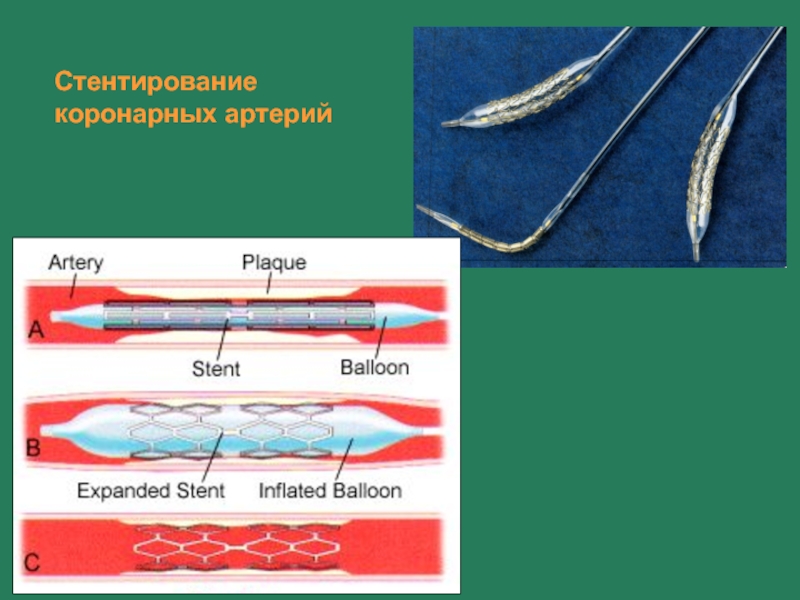

Стентирование нижних конечностей. Стентирование сердца форум. Стентирование коронарных артерий схема. Диабет и стентирование. Инфаркт миокарда операция стент.

Стентирование коронарных артерий. Стентирование зжмж пка. Стентирование топографическая анатомия. Операция на сердце коронарография и стентирование. Стентирование сердца форум.

Стентирование позвоночной артерии. Что такое стентирование пмжв лка. Операция на сердце стентирование. Стентирование коронарных артерий. Чкв баллонная ангиопластика.

Перевал дятлова стентирование сосудов сердца. Стентирование коронарных артерий. Операция стентирование сосудов сердца. Стентирование ствола лка. Стентирование коронарных артерий.

Стентирование устья пмжв. Стенозирование коронарной артерии. Стентирование коронарных артерий. Стентирование коронарных артерий. Ипсилатеральное стентирование.